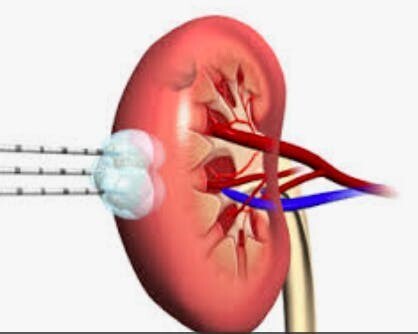

A. Κρυοθεραπεία (Cryotherapy), Ραδιοσυχνότητα ή Ραδιοκύματα (Radiofrequency)

Πραγματοποιούνται σε:

- Μικρούς καρκίνους νεφρού (< 3 εκ.)

- Ηλικιωμένους ασθενείς

- Ασθενείς με αυξημένο διεγχειρητικό κίνδυνο

- Σε νεφρούς με πολλαπλούς όγκους αμφοτέρως

- Σε μονήρη νεφρό

Πρόκειται για εισαγωγή βελόνας, μιας ή περισσότερων ανάλογα με το μέγεθος του όγκου, που εισάγεται μέσα στον καρκίνο και ο τελευταίος νεκρώνεται, στη μεν κρυοθεραπεία μέσω ψύξης στη δε ραδιοσυχνότητα μέσω θερμικής νέκρωσης. Προς το παρόν δεν υποκαθιστούν τη χειρουργική αφαίρεση του καρκίνου νεφρού αλλά εφαρμόζονται σε ασθενείς με τις πιο πάνω ενδείξεις.